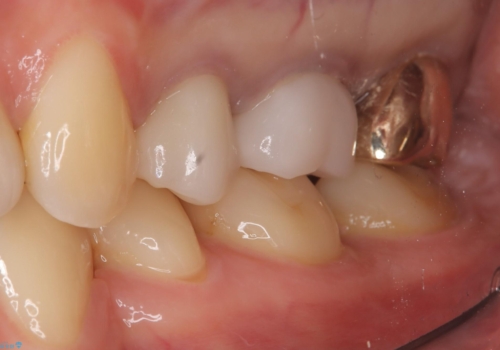

- 二次う蝕が心配という主訴で来院された患者さんです。

保険のメタルインレーから二次う蝕予防(保険のメタルインレーは腐食しやすかったり、適合があまり良くなかったりで二次的にう蝕がインレー下で広がってしまうことが多々あります。)のためのやり替えだったため、材料としてセラミックとゴールドを提案したところ、展延性に優れ違和感の少ないゴールドを選択されました。